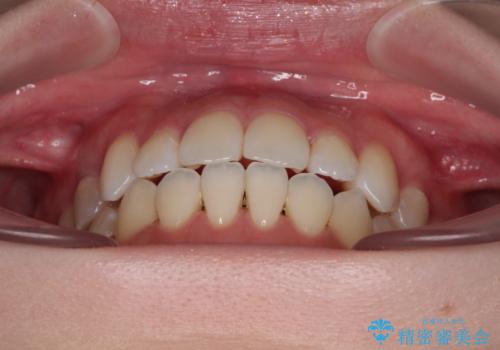

ワイヤー矯正での開咬改善には時間がかかります。

舌の突出癖改善のトレーニングをしっかりと行っていただき、上下前歯が接触する咬み合わせを達成することができました。